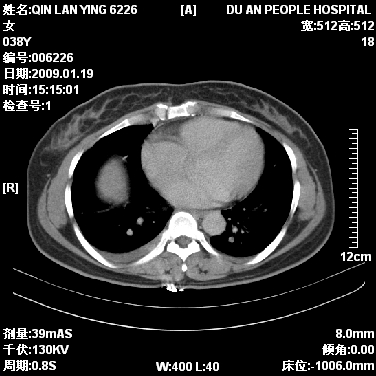

女,38岁,胸疼1个月。wbc:1万4

1)右肺中央型肺癌并右肺上叶阻塞性肺炎、节段性肺不张,纵隔淋巴结转移、右侧胸膜转移、肝脏转移。2)右侧胸腔少量积液。

本病例有几个容易诊断的地方:1、右肺上叶前段支气管闭塞,肺不张。2、淋巴结明显肿大。3、肝脏多个类圆形低密度影呈“牛眼征”改变,高度提示转移。

从影像学角度分析      右肺上叶中央型肺癌,并阻塞性不张、肺炎,纵隔淋巴结、膈顶淋巴结转移。

肝内两个大小不等低密度结节,内可见更低密度影,首先考虑肝内转移瘤,但联想到患者wbc1万4,建议楼主还是做个增强比较明确,除外肝脓肿的可能。